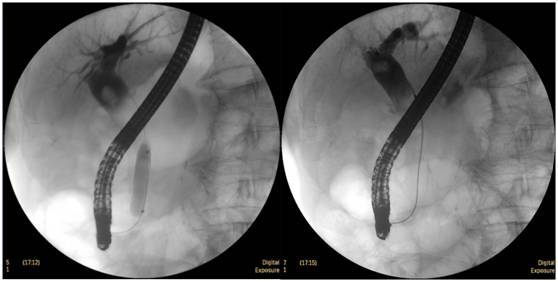

鼻膽管造影

立位注入造影劑,膽總管顯影好,稍擴(kuò)張,未見結(jié)石影。

膽總管結(jié)石

柱狀球囊擴(kuò)張完全,膽總管擴(kuò)張,下段見充盈缺損影。

柱狀球囊擴(kuò)張膽總管下段及乳頭(上圖為使用取石網(wǎng)籃取石)。